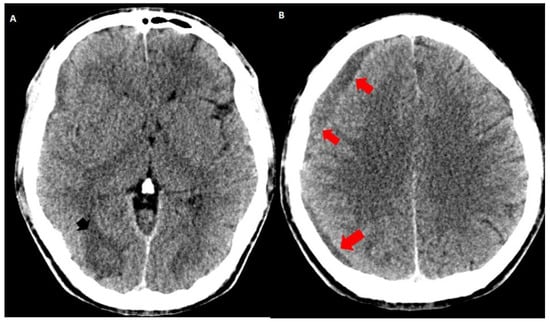

3.2. Imaging Studies